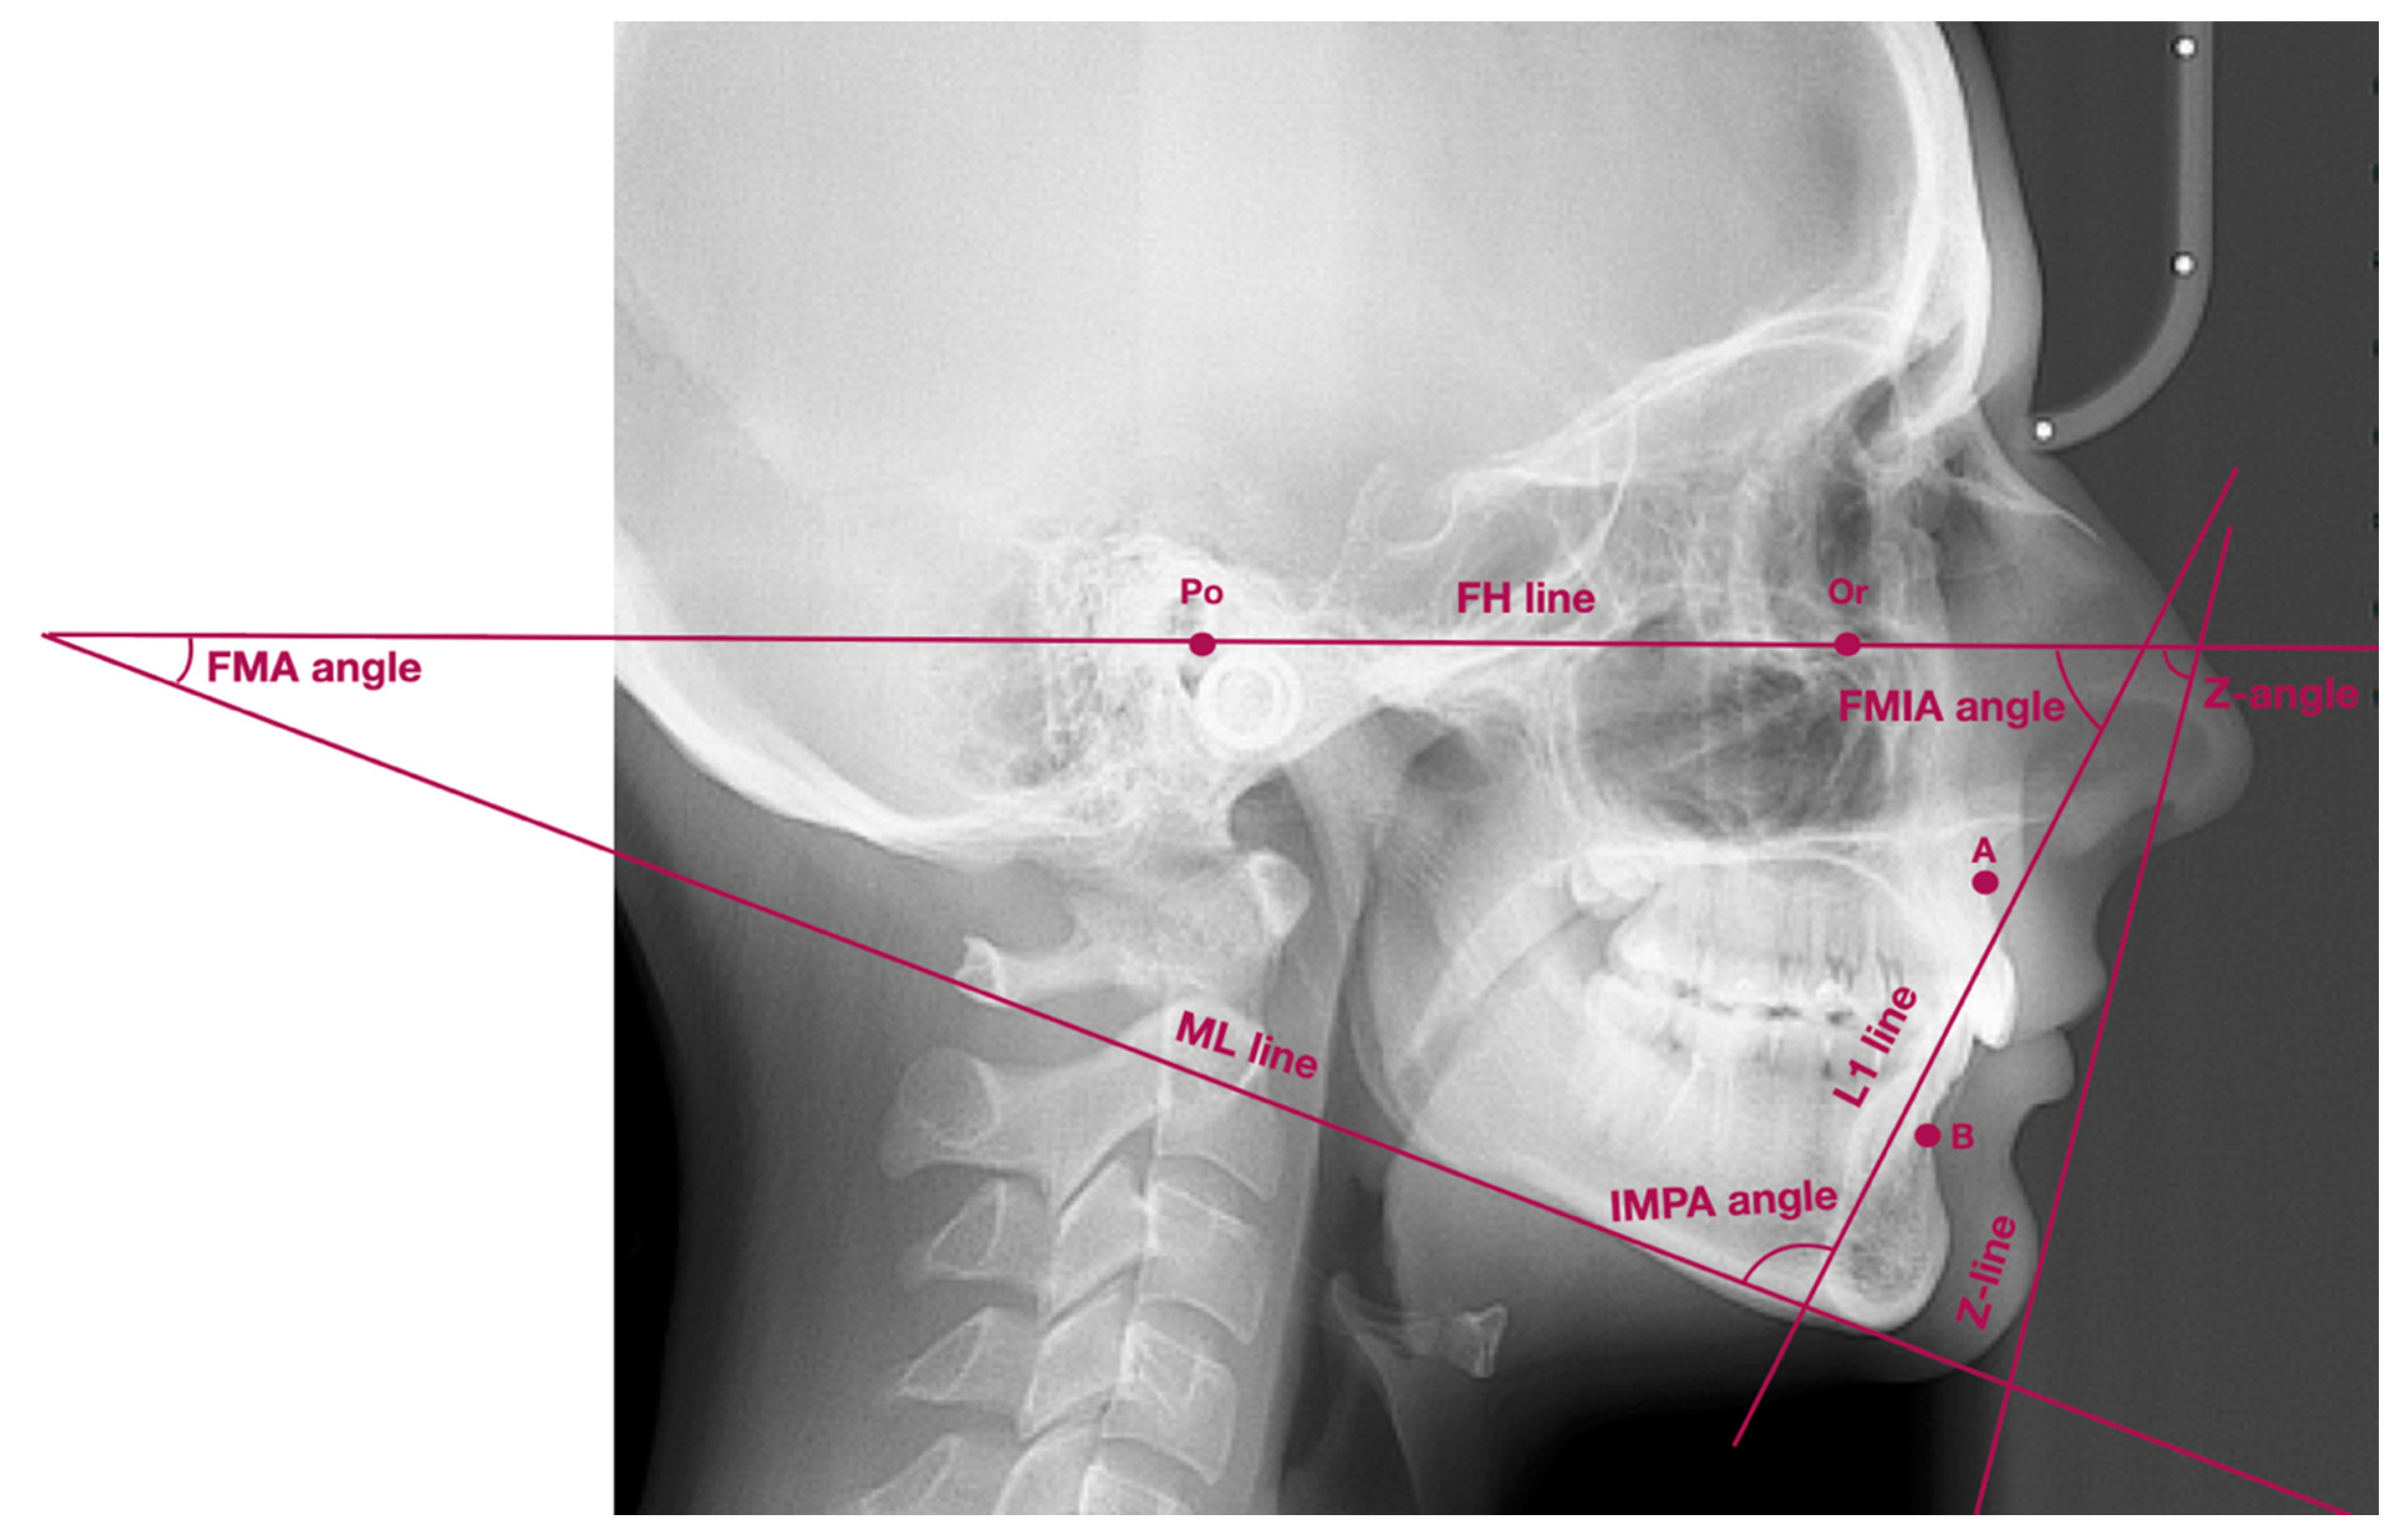

This kinda reminds me of the mew indicator line, indicator cheek line and what'd he go about evaluating SN line, FN plane and Cranial base angles

View attachment 4063432View attachment 4063433View attachment 4063434View attachment 4063436View attachment 4063438View attachment 4063439View attachment 4063440